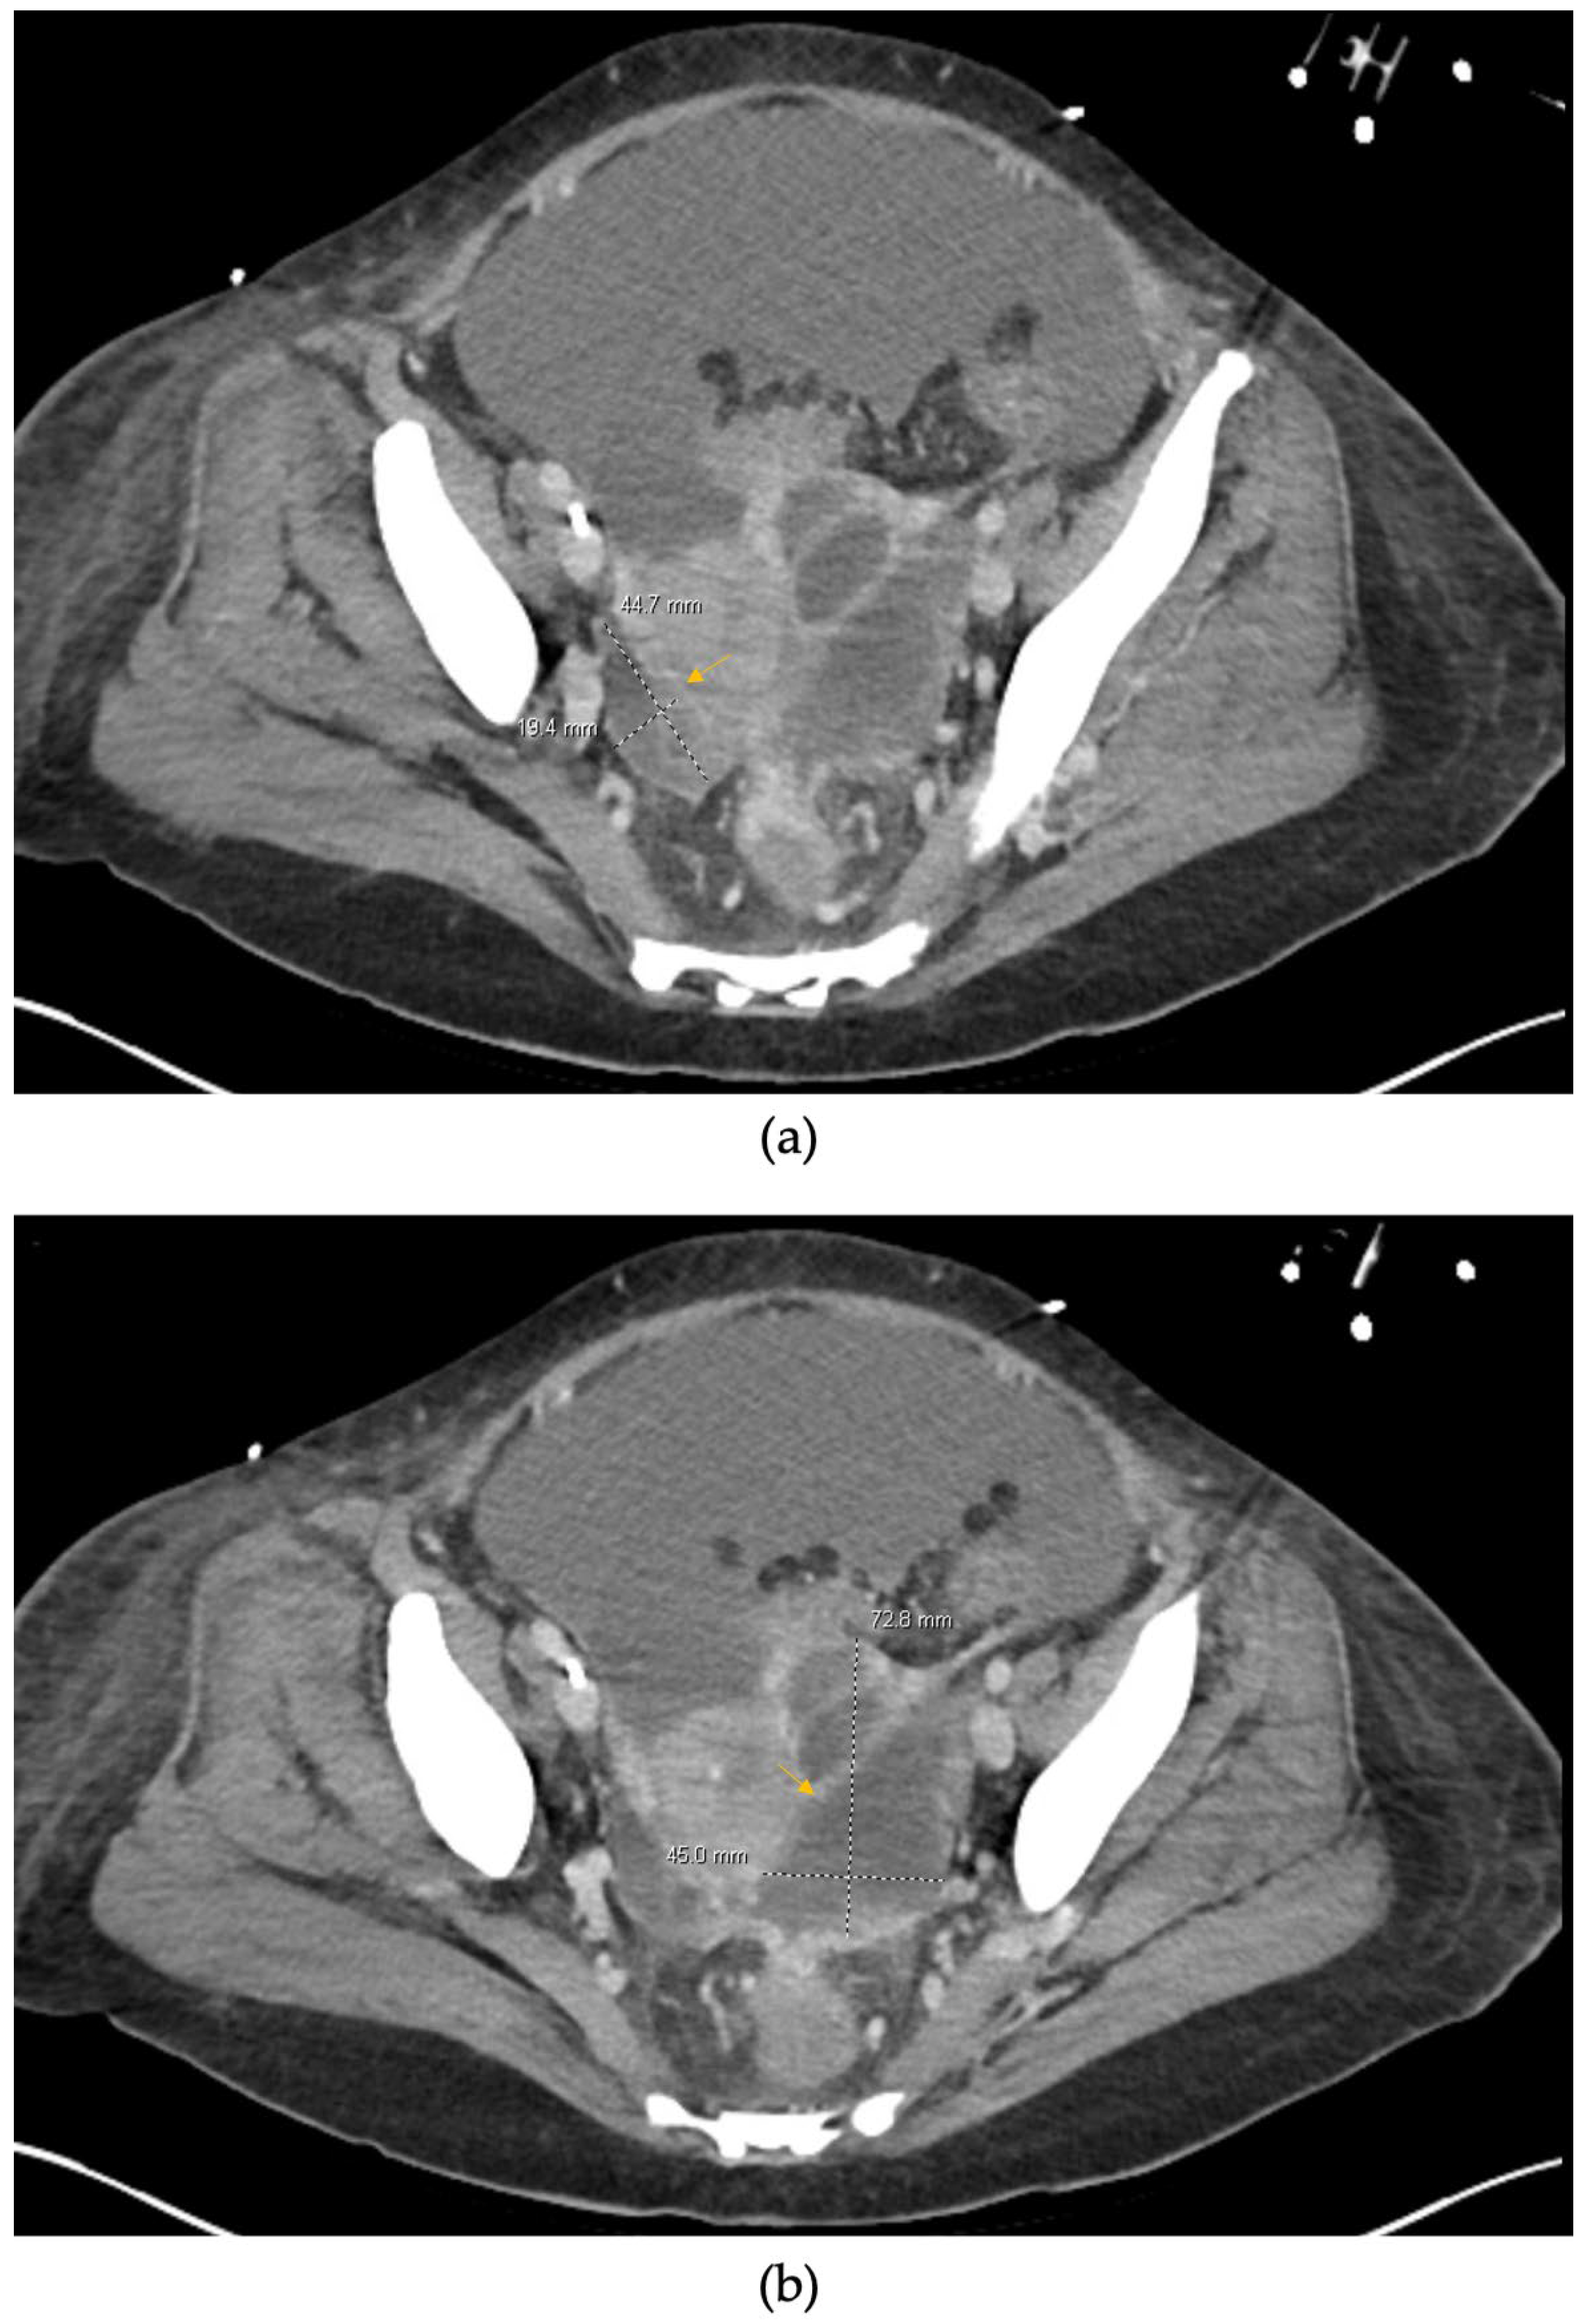

2. Case Presentation